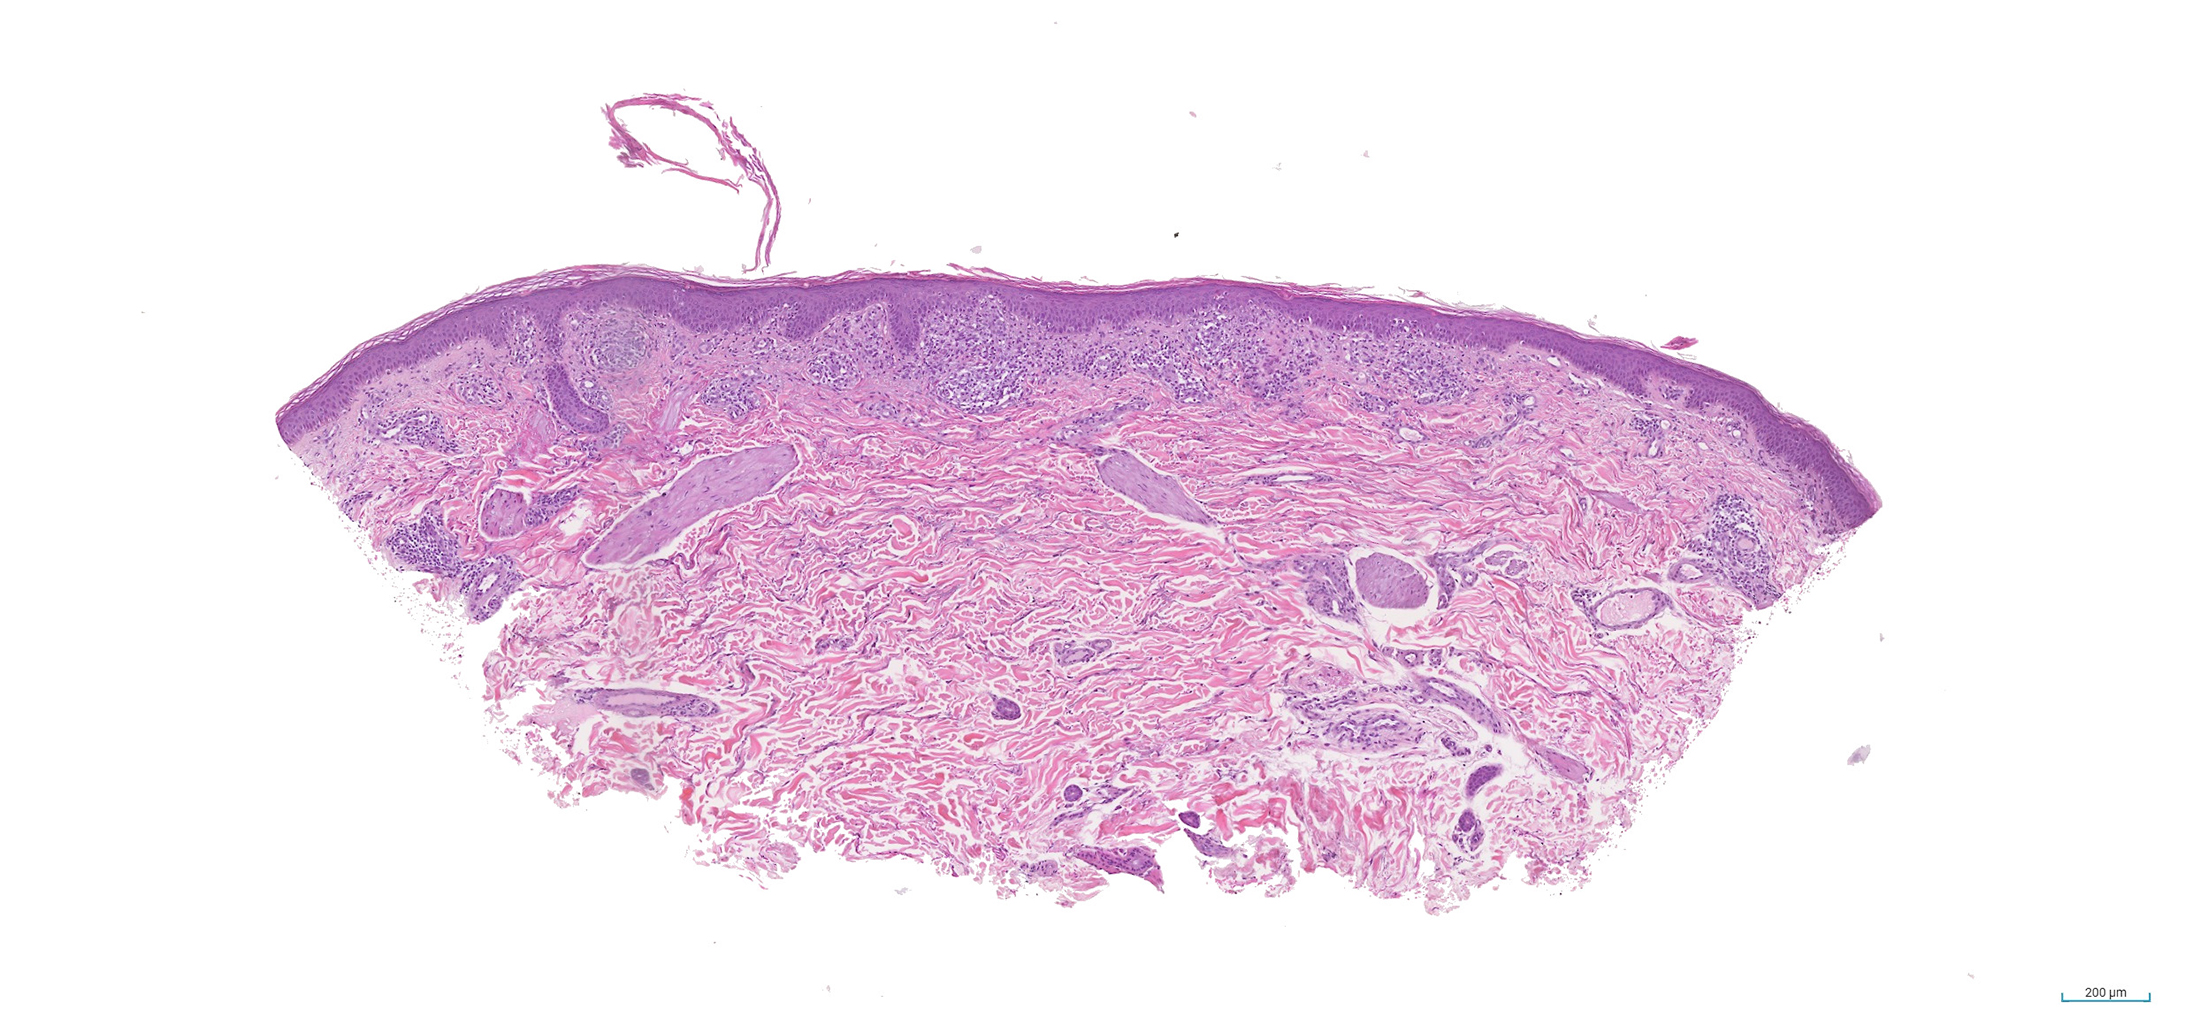

Histología: Se realizó una biopsia para hematoxilina-eosina (Figuras 6 a 10).